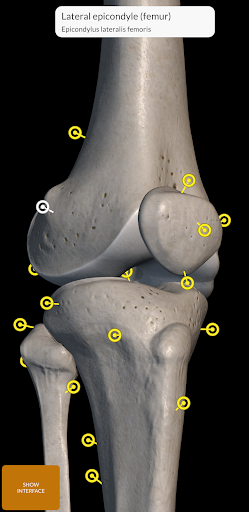

"Skeleton | 3D Atlas of Anatomy" is a next generation anatomy atlas in 3D which gives you availability of interactive highly detailed anatomical models!

Each bone of the human skeleton has been reconstructed in 3D, you can rotate and zoom in on each model and observe it in detail from any angle.

By selecting models or pins you will be shown the terms related to any specific anatomical part, you can select from 12 languages and show the terms in two languages simultaneously.

• Rotate and Zoom every model in the 3D space

• Interactive Pin allow visualization of the term relative to every anatomical detail